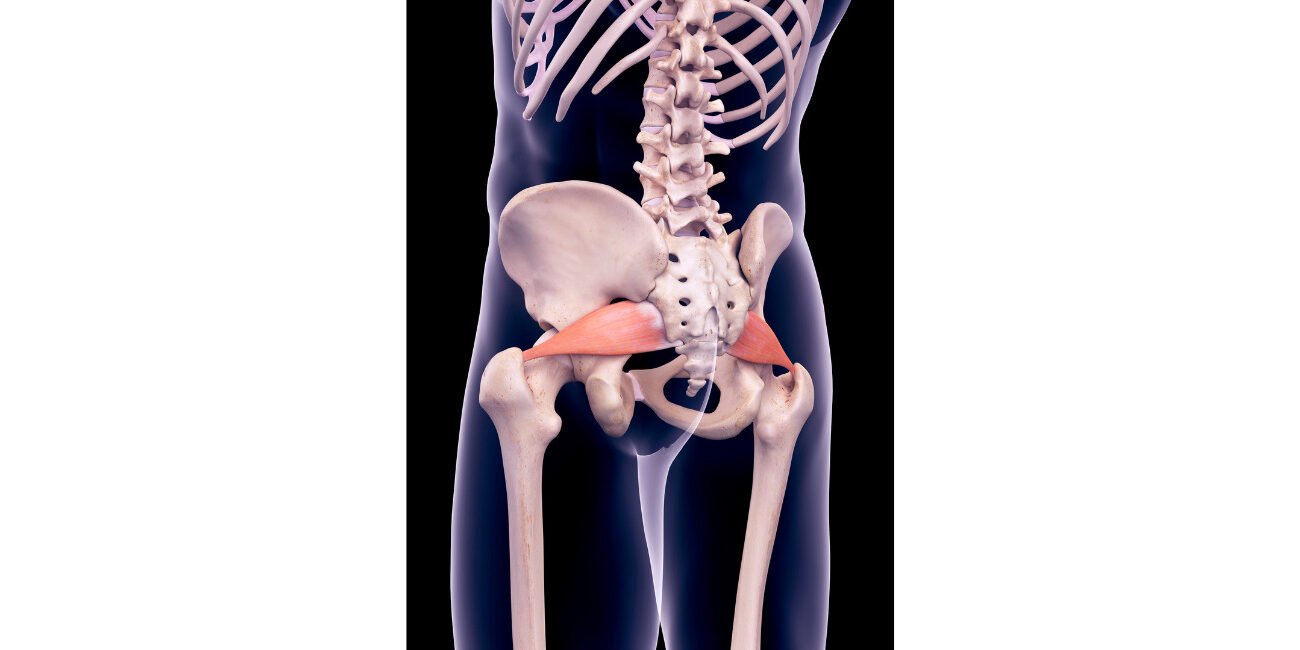

El síndrome piramidal o piriforme es una condición dolorosa que afecta al músculo piriforme, ubicado en la región glútea. Este músculo juega un papel importante en la estabilidad y el movimiento de la cadera, ya que permite la rotación externa de la misma. Cuando el músculo piriforme se inflama o se irrita, puede comprimir el nervio ciático, lo que lleva a la aparición de los síntomas característicos de este síndrome.

El tratamiento del síndrome piramidal o piriforme se centra en aliviar el dolor, reducir la inflamación y mejorar la función del músculo piriforme (extensión, rotación externa y abducción del fémur cuando la pelvis está fija). Algunas opciones de tratamiento incluyen: